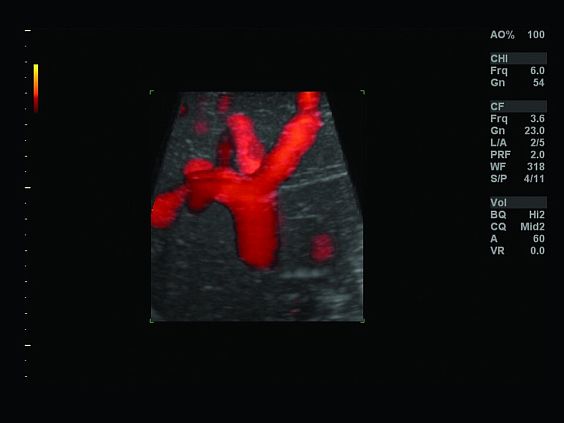

Клинические изображения

- B-Flow / Color B-Flow - режим недопплеровской визуализации кровотока

- Q-analysis Option for Elastography and CF/PDI Quantification - программа количественного анализа для эластографии и анализа васкуляризации в режиме ЦДК и ЭД

- Color Flow Quantification - программа количественой оценки кровотока

Ультразвуковой аппарат LOGIQ S7 XDclear предназначен для использования специалистами из различных областей диагностики. Его расширенный функционал включает такие возможности как B-Flow — недопплеровская технология отображения кровотока в B-режиме, компрессионная эластография (качественная и полуколичественная), количественный анализ васкуляризации, функцию В-Steer+ — изменение угла наклона УЗ луча в B-режиме, 3D/4D диагностику и мультимодальную визуализацию.